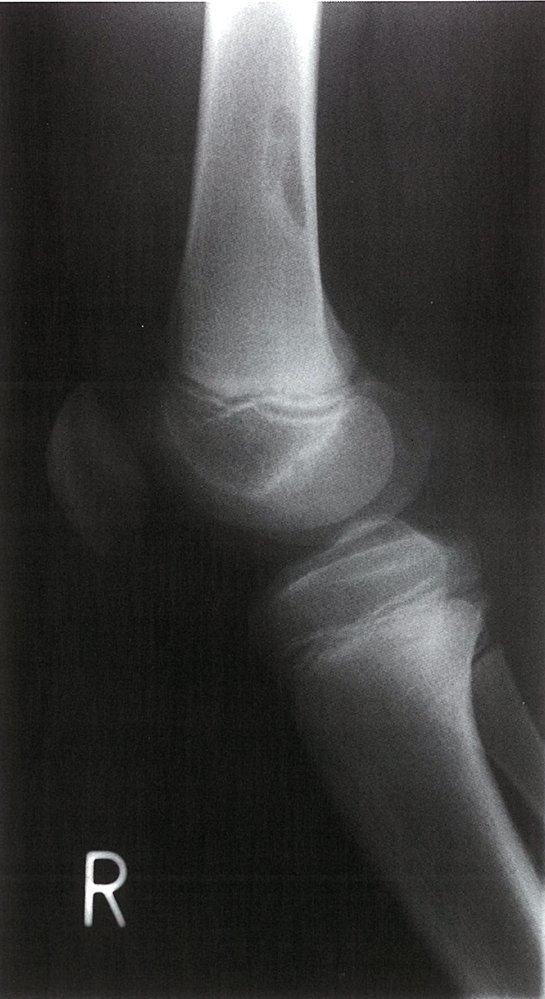

• Description: benign but locally aggressive tumor composed of giant cells that arise from the bone marrow [1]

• Epidemiology: peak incidence between 20 and 40 years

• Clinical features

• Found in the epiphysis or metaphysis of long bones (especially knee region)

• Pathological fractures

• Local pain and swelling

• Limited range of motion

• Diagnostics

• X-ray: multicystic osteolytic lesions (soap-bubble appearance)

• Treatment: curettage and bone grafting or en-bloc resection to minimize recurrence rate

• Prognosis: risk of malignant degeneration increases with age; may spread to the lungs